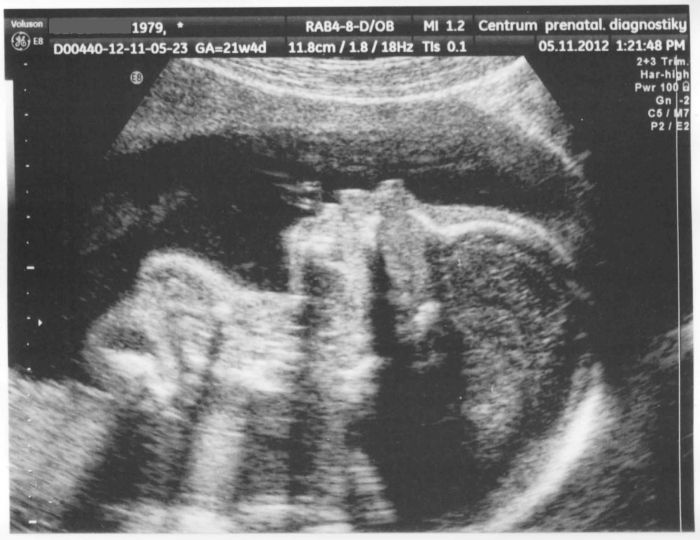

Připojuji foto našeho mrňouska

Ahoj holky, také mám za sebou druhý screening, a to v Brně na Veveří. Vše je v pořádku a hlásím také chlapečka. Marci: nic se neplatí, pokud máš žádanku od své gynekoložky. Možná by Ti to ale pojišťovna proplatila i bez ní. Je to velmi podrobný ultrazvuk. Doktor Ti ukáže profil miminka, oči, uši, dásně, základ na zuby, srdce (pustí Ti nahlas i zvuk, aby jsi slyšela ozvy), ledviny, močový měchýř.. zkrátka vše. Pokud chceš znát pohlaví, řeknou Ti i tohle. Pak Ti nabídnou fotečku za 50,- Nakonec dostaneš krátkou zprávu. To že je mimi v pořádku zjistíš ale už během vyšetřování. Doktor Ti bude vše popisovat. My byli u MUDr. Vlašína, byl moc příjemný. Já pohlaví nejdřív neviděla, což přišlo doktorovi i přítelovi vtipné..